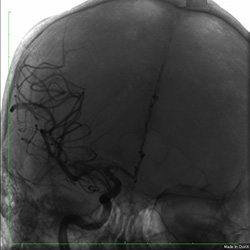

— Проводник был проведен через окклюзию в дистальный отдел правой средней мозговой артерии. Стент-ретривер заведен в область тромба правой средней мозговой артерии. После удаления стента-ретривера получено большое количество тромботических масс (рис.2). На контрольной ангиограмме кровоток в бассейне правой внутренней сонной, передней и средней мозговых артерий полностью восстановлен (рис.3).

![]() рис 3. Кровоток в бассейне правой внутренней сонной, передней и средней мозговых артерий восстановлен |